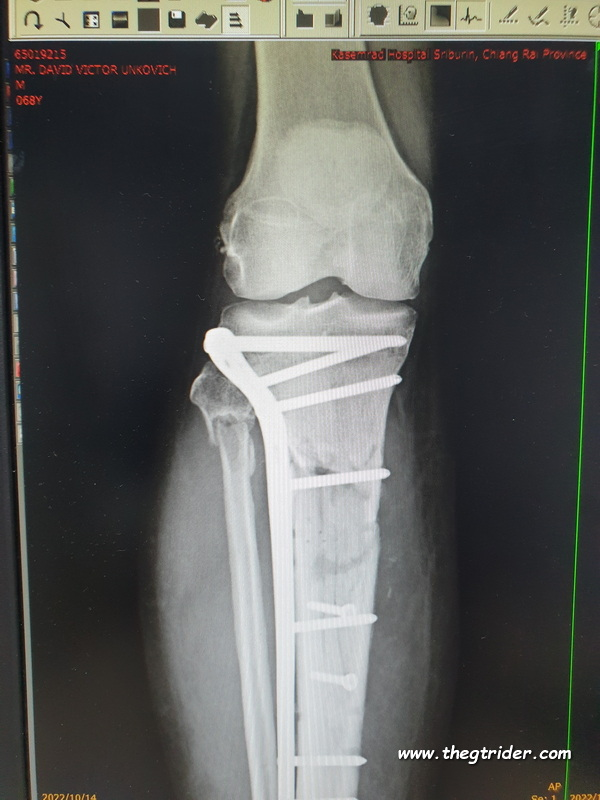

Finally looking good, almost perfect. The bones have knitted.

Xray on 6th January 2023.

From the accident, 204 days or 6 months, 21 days excluding the end date.

1673093582146.png

How the bits & pieces looked in October

1665913260172-png.149810

and I can tell you it feels great to have a leg that feels like a whole functioning leg, although we've got to build up some strength in it still.

I cant wait to get back riding big yellow.